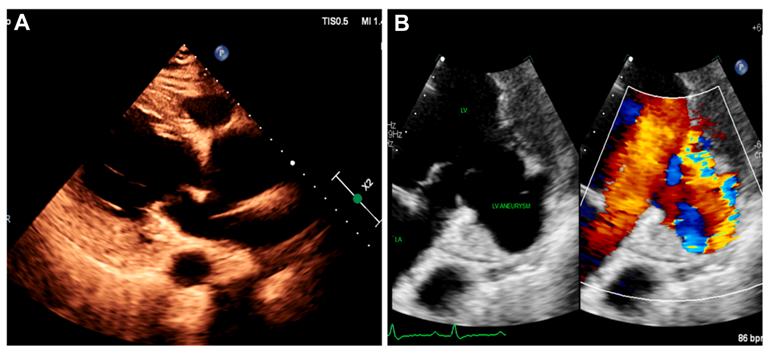

图1:经胸超声心动图

第1天:经胸

第2天:冠状动脉CTA显示右冠状动脉(RCA)巨大动脉瘤,最大直径42 mm,累及RCA中段至远段,瘤壁钙化,未见冠脉开口处梗阻。瘤样扩张的RCA发出瘘性交通,直接引流入左心室下壁基底部腔内。动脉瘤腔内未见附壁血栓。另可见真性左室下壁基底部室壁瘤,大小约3.2×2.1 cm,室壁连续性完整,所有心肌层均受累并呈透壁性变薄。未见假性室壁瘤表现。同时可见升主动脉扩张(直径49 mm)(图2)。